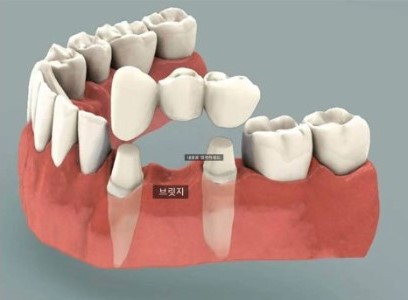

결손치가 있을 때 가장 흔히 생각하는 치료 방법은 다음과 같습니다.

1. 공간을 확보한 뒤, 그 자리에 임플란트 식립

2. 공간을 확보한 뒤, 양 옆 치아를 많이 삭제하여 브릿지(보철물) 제작

747569ca512315b293293d02a0866f62_1763604888_1668.jpg

그리고 세 번째 방법이 바로,

1. 교정치료를 통해 공간을 닫아주는 방법 입니다.